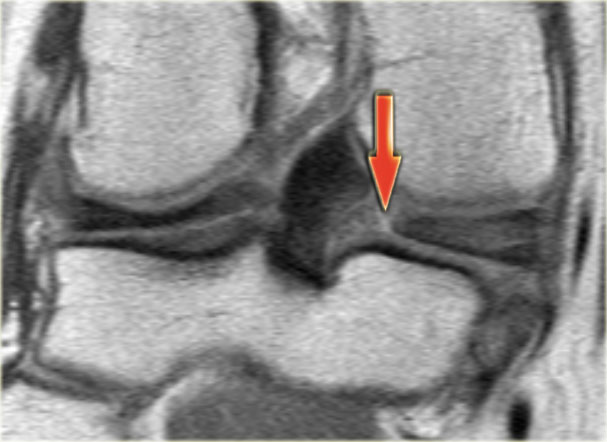

Như bạn đã đoán được qua tiêu đề của đoạn này, đây là một trường hợp sụn chêm lật (flipped meniscus).

Sụn chêm lật là một dạng đặc biệt của rách dạng quai xô (bucket-handle tear).

Sụn chêm lật xảy ra khi mảnh vỡ của sừng sau bị lật ra phía trước, khiến sừng trước của sụn chêm có vẻ to hơn bình thường.

- Sừng sau quá nhỏ và sừng trước có vẻ to hơn với đường viền không đều.

- Thoạt nhìn có vẻ như có một đường rách dọc ở sừng trước, nhưng thực chất phần sau của cấu trúc này chính là phần lật của sừng sau bị rách.

Cấu trúc phía trước là sừng trước.

Cũng cần lưu ý tình trạng phù tủy xương khu trú và dấu ấn lõm sụn khớp. - Cấu trúc phía trước là sừng trước.